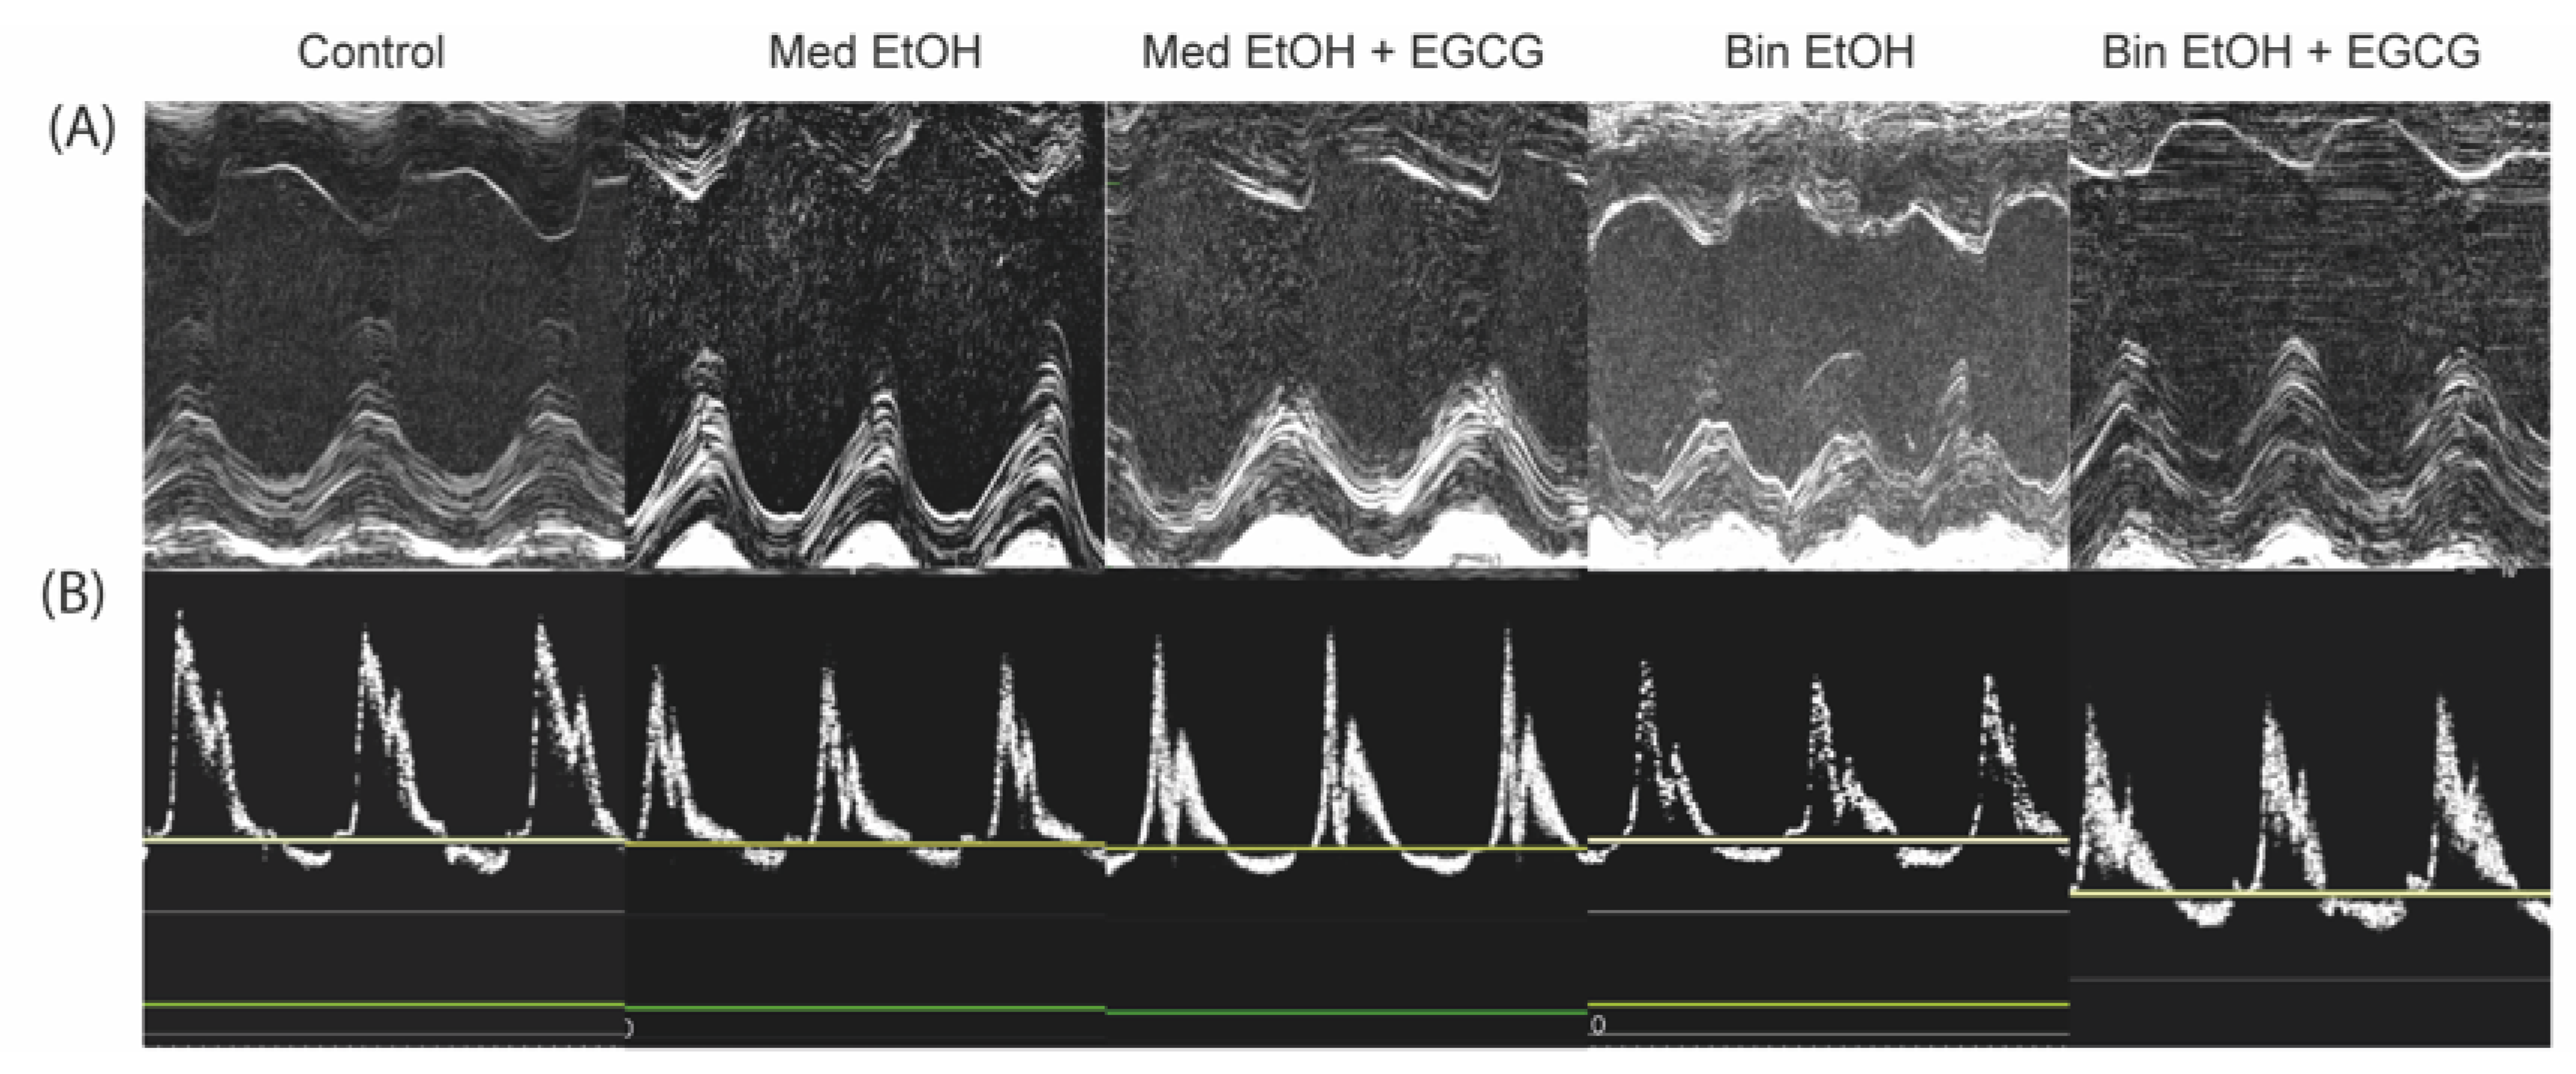

3.2. Echocardiographic Analysis